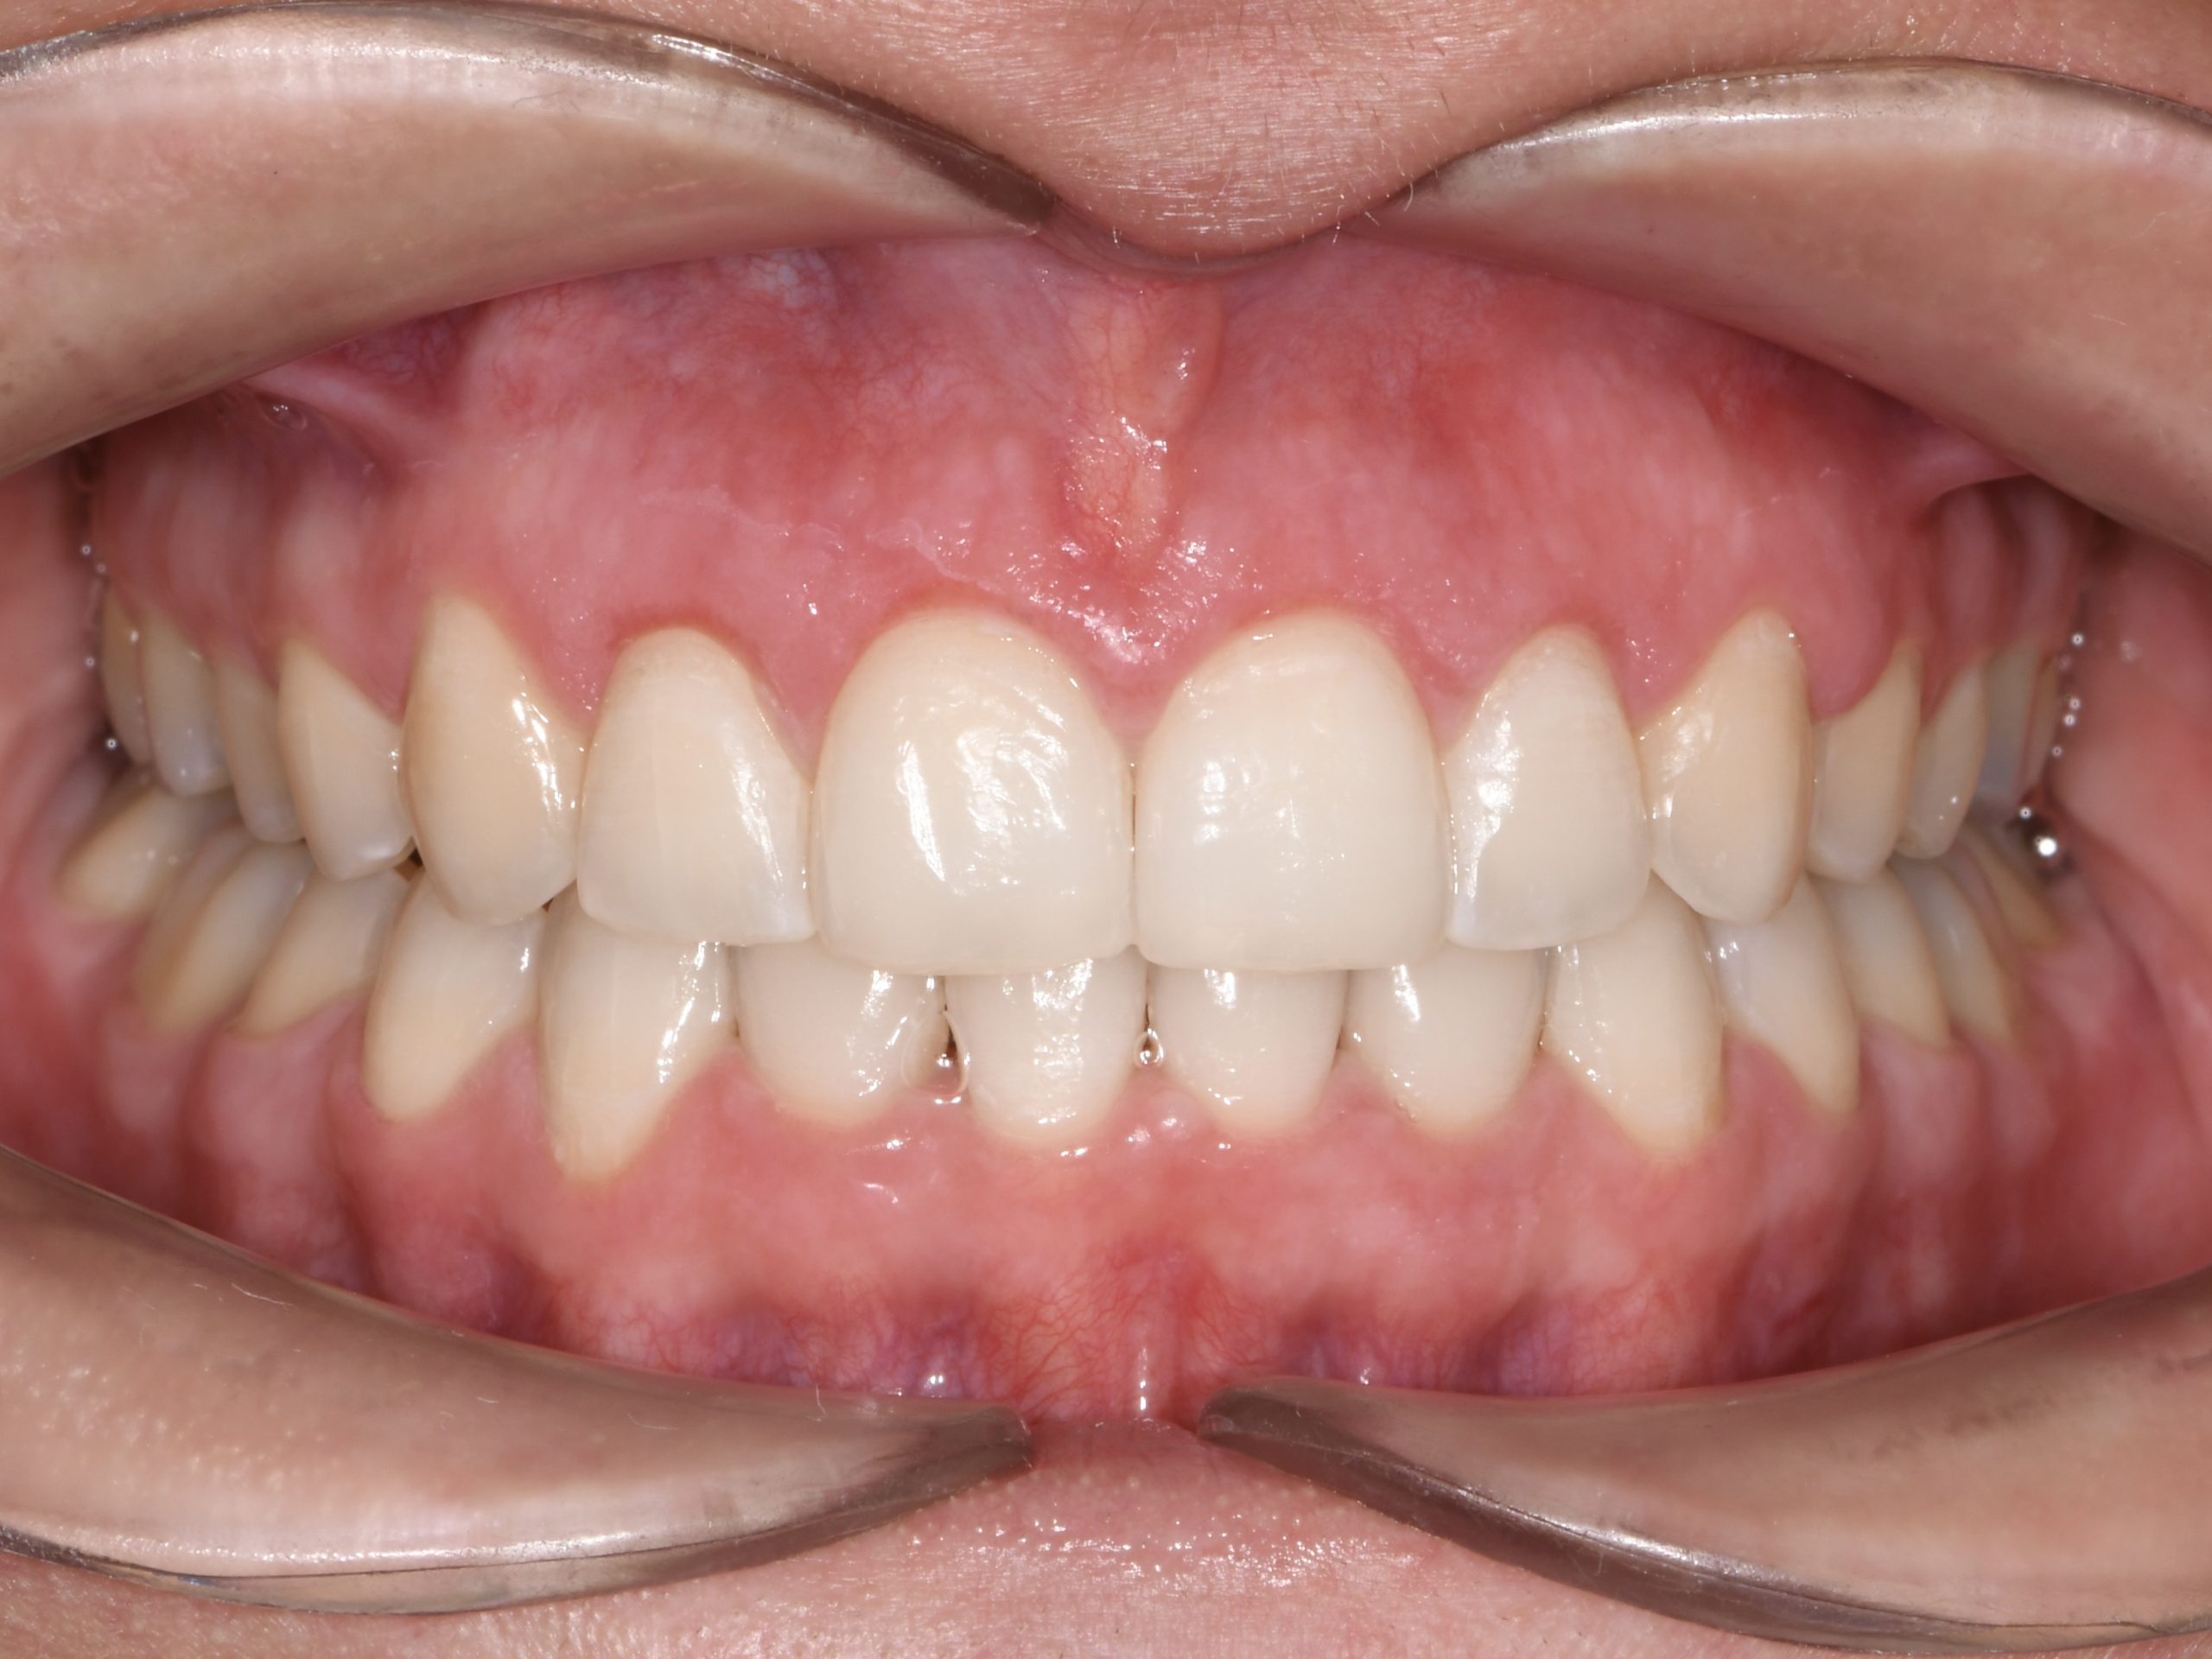

Az elmúlt évekből rengeteg szakmai referenciát tudnánk bemutatni, amelyek különböző fogszabályozási problémákat oldottak meg. Válogatva a több száz esetből, ezen az oldalon olyan képeket, információkat igyekeztünk bemutatni, amelyeknek a segítségével a jövőbeni pácienseinknek azt tudjuk üzenni: A Te fogsorod is lehet gyönyörű!

(Képeket a Pácienseink külön írásos beleegyezésével mutatjuk be!)